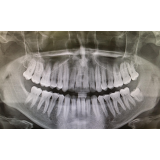

Dişlerin Yeniden Büyümesini Sağlayan İlaç Geliştiriliyor

Bilim adamları, potansiyel olarak dişlerin yeniden büyümesini sağlayabilecek çığır açan bir ilacın geliştirilmesinde önemli adımlar atıyorlar.